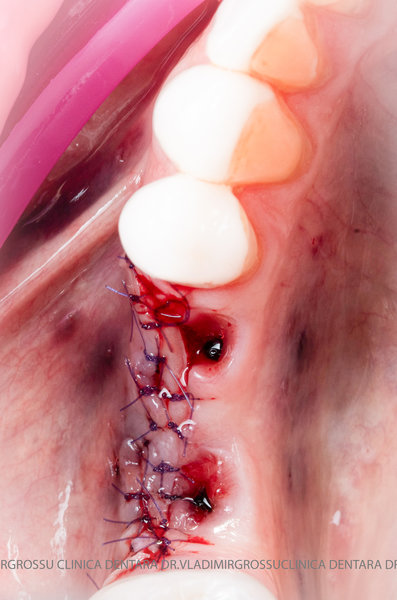

Un element esențial în procedura de aditie osoasă este utilizarea membranelor biologice, care izolează materialul osos de țesuturile moi (gingie) pe durata procesului de vindecare. Cele mai recomandate sunt membranele resorbabile din colagen sau pericard.

Aditia gingivală este o procedură chirurgicală ce corectează diverse probleme estetice și funcționale, cum ar fi recesiunea gingivală. În implantologia modernă, aditia de țesut moale este utilizată aproape în fiecare intervenție de inserție a implantului dentar pentru a asigura un aspect estetic natural și o bună integrare a implantului în cavitatea bucală.